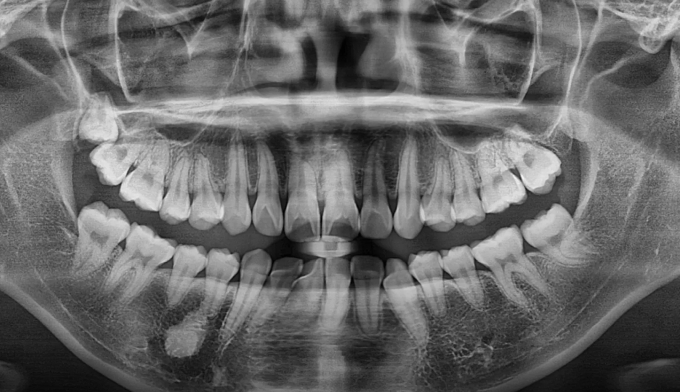

처음 교정치료를 위해 내원하였을때 확인할 수 있었던 것은 화살표로 표시한 부분의 사랑니 맹출이상 이었습니다.

사랑니가 그 앞 어금니쪽으로 잘못 나오게되면서 멀쩡한 어금니의 뿌리를 다 녹이고 있었습니다.